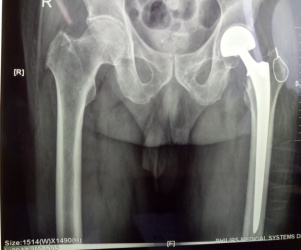

? ? ? ?7月26日,由張富軍主任主刀、張浩主治醫(yī)生協(xié)助及麻醉科龐曉宏主任及陳波副主任醫(yī)師密切配合,成功為三位高齡患者實(shí)施“人工股骨頭置換術(shù)”。

? ? ? 考慮到患者均為高齡,且合并內(nèi)科疾病,麻醉選擇硬腰聯(lián)合,第一位股骨頸骨折患者8點(diǎn)進(jìn)入手術(shù)室,血壓高至210/110mmHg,麻醉科龐曉宏主任、陳波副主任醫(yī)師緊急商討,積極處置,患者血壓穩(wěn)定在130/80mmHg左右,上午9點(diǎn)手術(shù)開始,27分鐘完成手術(shù),在患者家屬焦急等待中于10點(diǎn)整推出手術(shù)室;第二位、第三位粗隆間骨折行人工關(guān)節(jié)置換手術(shù)+骨折復(fù)位內(nèi)固定術(shù)均1小時(shí)內(nèi)完成,術(shù)后患者病情穩(wěn)定。忙碌一天的我們顧不得疲憊,晚上6點(diǎn)張富軍主任及麻醉科龐曉宏主任、陳波副主任醫(yī)師再次巡視術(shù)后患者,制定術(shù)后鎮(zhèn)痛、抗凝方案,確?;颊咂椒€(wěn)、無痛度過圍手術(shù)期。在髖、膝關(guān)節(jié)快速康復(fù)理念指導(dǎo)下,三位患者手術(shù)切口均采用美容縫合,于次日手把手指導(dǎo)患者正確下床活動方法,真正做到無痛、無管、早下地、免拆線的快速康復(fù)。目前三位患者均恢復(fù)滿意,無術(shù)后嚴(yán)重并發(fā)癥發(fā)生?;颊呒凹覍俑屑とf分,他們的笑容就是我們最大的欣慰。